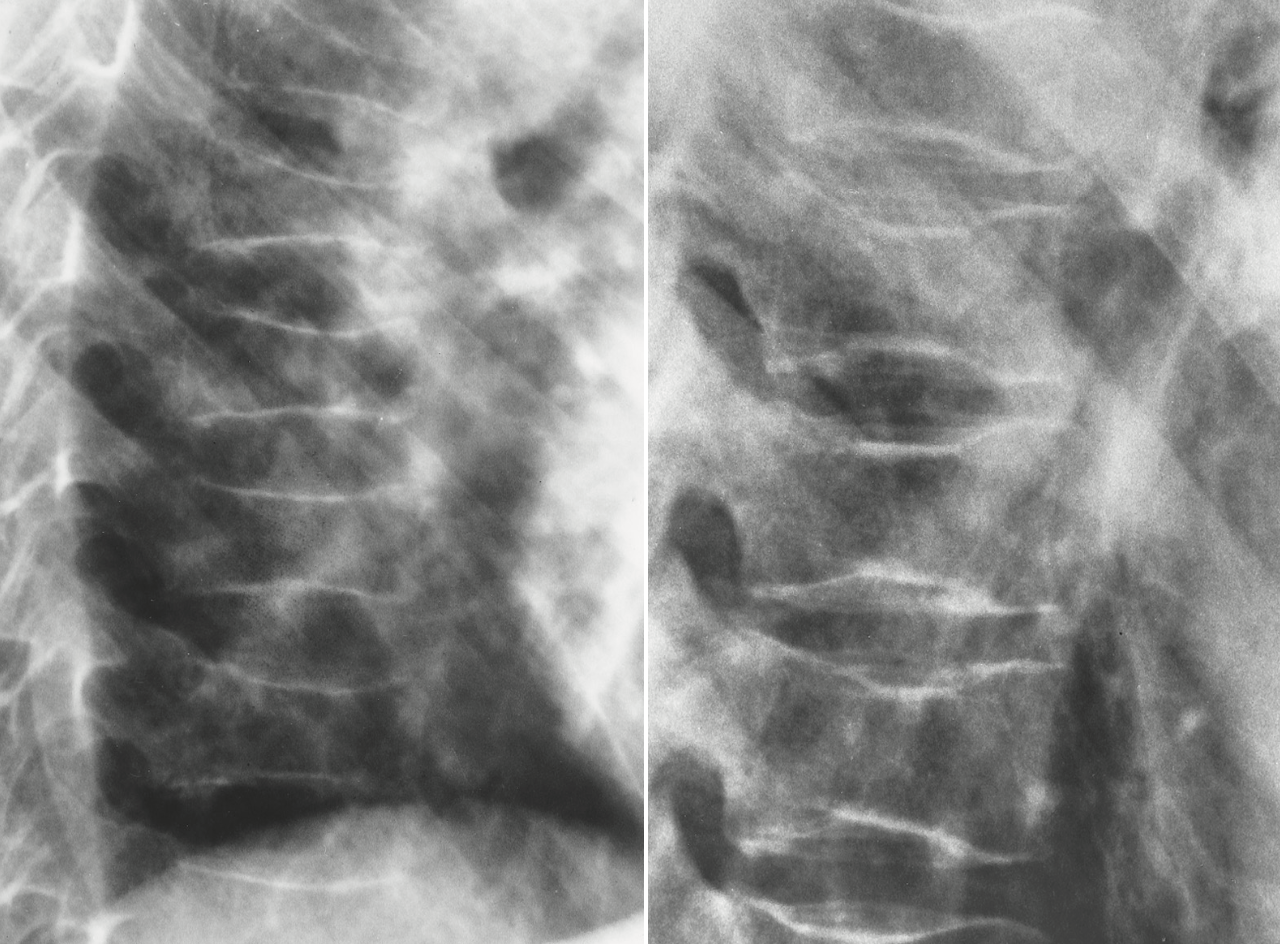

fish vertebrae

sickle cell anemia appearance